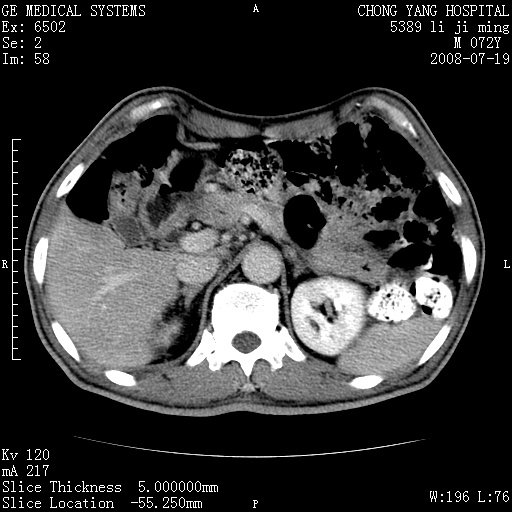

以下是引用zjzjr在2008-7-19 20:57:00的发言:[br]胰头增大,边缘模糊,周围可见渗出影,右侧肾前筋膜增厚.支持胰腺炎.

以下是引用yangyudong333在2008-7-20 6:56:00的发言:[br]胰腺增大尤以胰头明显,边缘模糊,周围可见渗出影,右侧肾前筋膜增厚,肠管於涨.支持胰腺炎

以下是引用不学无术在2008-7-19 23:15:00的发言:[br]胰腺增大尤以胰头明显,边缘模糊,周围可见渗出影,右侧肾前筋膜增厚,肠管於涨.支持胰腺炎